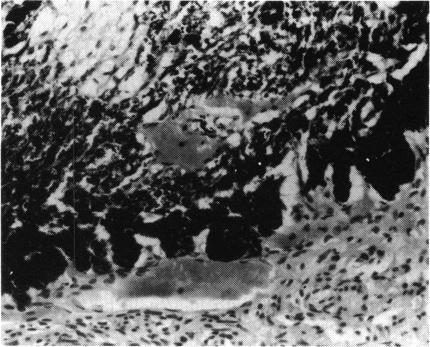

Two sibships, each with two affected males but no other affected family members, are described. All four patients at birth had small eyes with white masses visible behind clear lenses. Support for a diagnosis of Norrie's disease lies in the probable mental retardation and sudden death of one child and mental retardation in the other in one of the families, and strong support in the sensorineural deafness in one child in the other family. A necropsy was performed on the dead child. Both eyes showed the retinae to be totally non-attached. The optic nerves were thin. If the diagnosis is Norrie's disease (highly probable), the birth of the second affected child in each family supports the postulate of a mutation in the X chromosome of a germ cell of a maternal grandparent or an earlier maternal ancestor, no previous member of the family having been affected. That implies a 50% risk of the disease in future male siblings and a 50% risk of the carrier state in female sibs. When only one child is affected, the explanation could also be a mutation in that individual. Given Norrie's disease, we have calculated a mutation rate of 3.9 per million chromosomes in the Scottish population--remarkably similar to the mutation rates calculated for many dominant diseases. A diagnosis of autosomal recessive non-attachment of retina implies a 25% risk to later siblings.

本文描述了两个家系,每个家系中有两名患病男性,无其他患病家庭成员。所有四名患者出生时眼睛均较小,在透明晶状体后可见白色肿物。支持诺里病诊断的依据包括:其中一个家系中有一名儿童可能存在智力发育迟缓及猝死情况,另一名儿童存在智力发育迟缓;另一个家系中有一名儿童患有感音神经性耳聋,这为诊断提供了有力支持。对死亡儿童进行了尸检。双眼视网膜均完全脱离。视神经纤细。如果诊断为诺里病(极有可能),每个家系中第二名患病儿童的出生支持了这样一种假设:即 maternal grandparent(外祖父母中的一方)或更早的母系祖先的生殖细胞X染色体发生了突变,该家族中之前没有成员患病。这意味着未来男性同胞患病风险为50%,女性同胞成为携带者的风险为50%。当只有一名儿童患病时,也可能是该个体发生了突变。考虑到诺里病,我们计算出苏格兰人群中每百万条染色体的突变率为3.9——这与许多显性疾病计算出的突变率非常相似。诊断为常染色体隐性遗传性视网膜脱离意味着后续同胞有25%的患病风险。